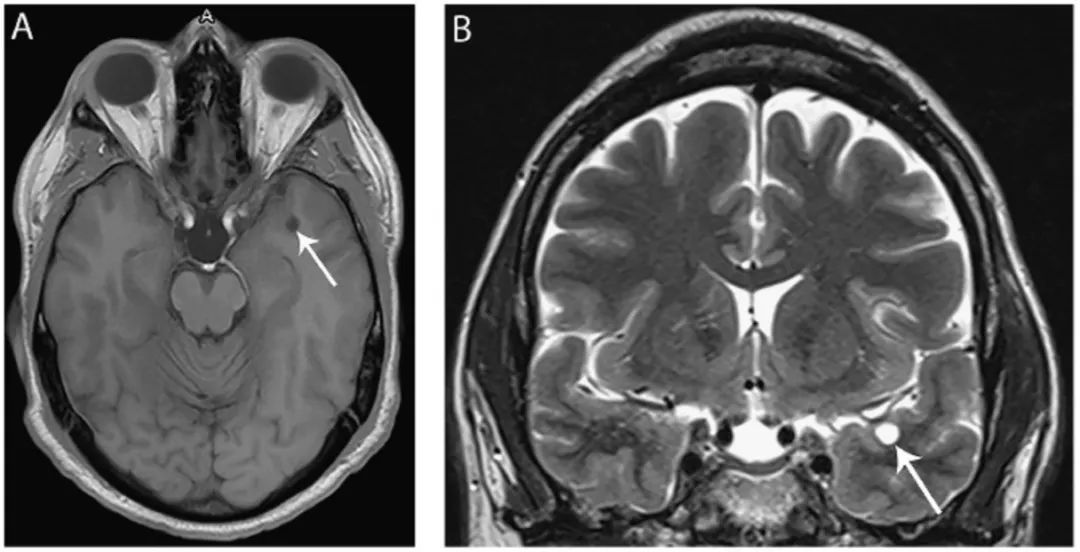

图3 脉络膜裂神经上皮囊肿

(A) 冠状位T2WI显示位于海马区上方,起源于脉络膜裂的囊肿(箭头);(B)FLAIR像显示同一囊肿(箭头)位于中脑外侧、颞叶内侧。